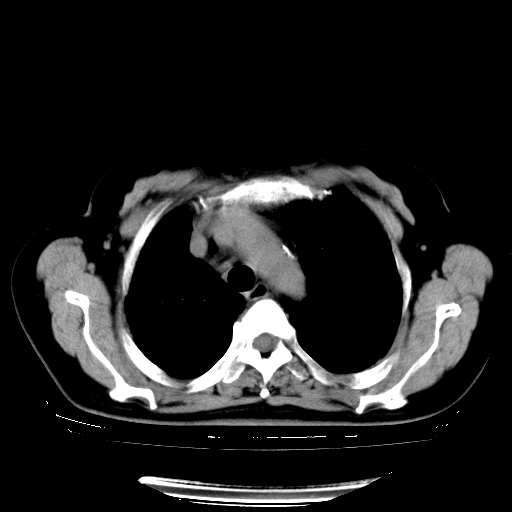

以下是引用zhangzhongshou在2008-3-22 12:52:00的发言:[br]1、右侧液气胸。[br]2、腹水。建议进一步检查。

以下是引用鲁巨ct在2008-3-22 14:10:00的发言:[br]1、右侧液气胸,右中下叶节段性不张。[br]2、腹水,建议上腹部ct检查

以下是引用zjzjr在2008-3-22 17:19:00的发言:[br]1、右侧液气胸,右下叶节段性不张。[br]2、腹水,建议上腹部ct检查